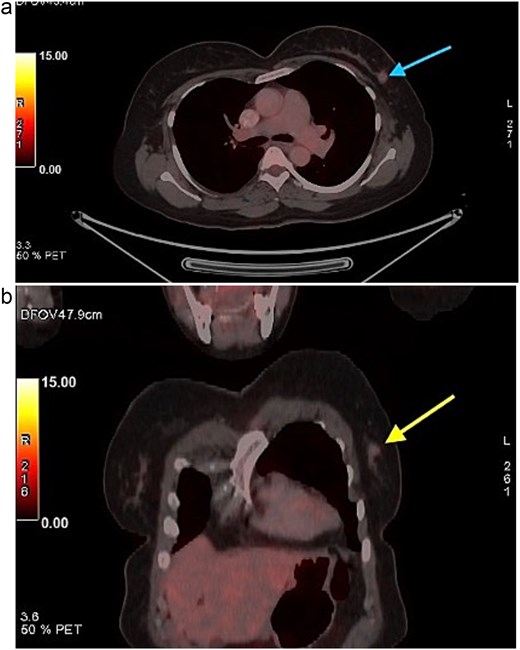

A 58-year-old woman with no relevant family history underwent routine health screening during which a left breast lump was detected. Mammography showed a high density spiculated lesion in the upper outer quadrant (BIRADS 4c/5) (Fig. 1a and b). Ultrasound demonstrated a 1.0 × 1.1 cm spiculated, heterogeneous hypoechoic lesion (BIRADS 4c). FDG positron emission tomography computed tomography (PET CT) revealed mild uptake confined to the breast lesion (SUVmax ~2.5) with no FDG avid axillary nodes or distant disease (Fig. 2a and b). Ultrasound guided FNAC revealed infiltrating ductal carcinoma (Yokohama Category 5) with cohesive clusters and scattered malignant ductal epithelial cells showing nuclear overlapping, moderate pleomorphism, conspicuous nucleoli, and moderate cytoplasm in a hemorrhagic background.

Mammography of the left breast. (a) Craniocaudal view showing a high density spiculated lesion in the upper outer quadrant, consistent with BIRADS 4c/5, suspicious for malignancy. (b) Mediolateral oblique view demonstrating the same spiculated, high density lesion in the upper outer quadrant, corresponding to the known carcinoma (BIRADS 4c/5).